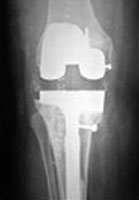

Complex Knee

Before Surgery

After Surgery